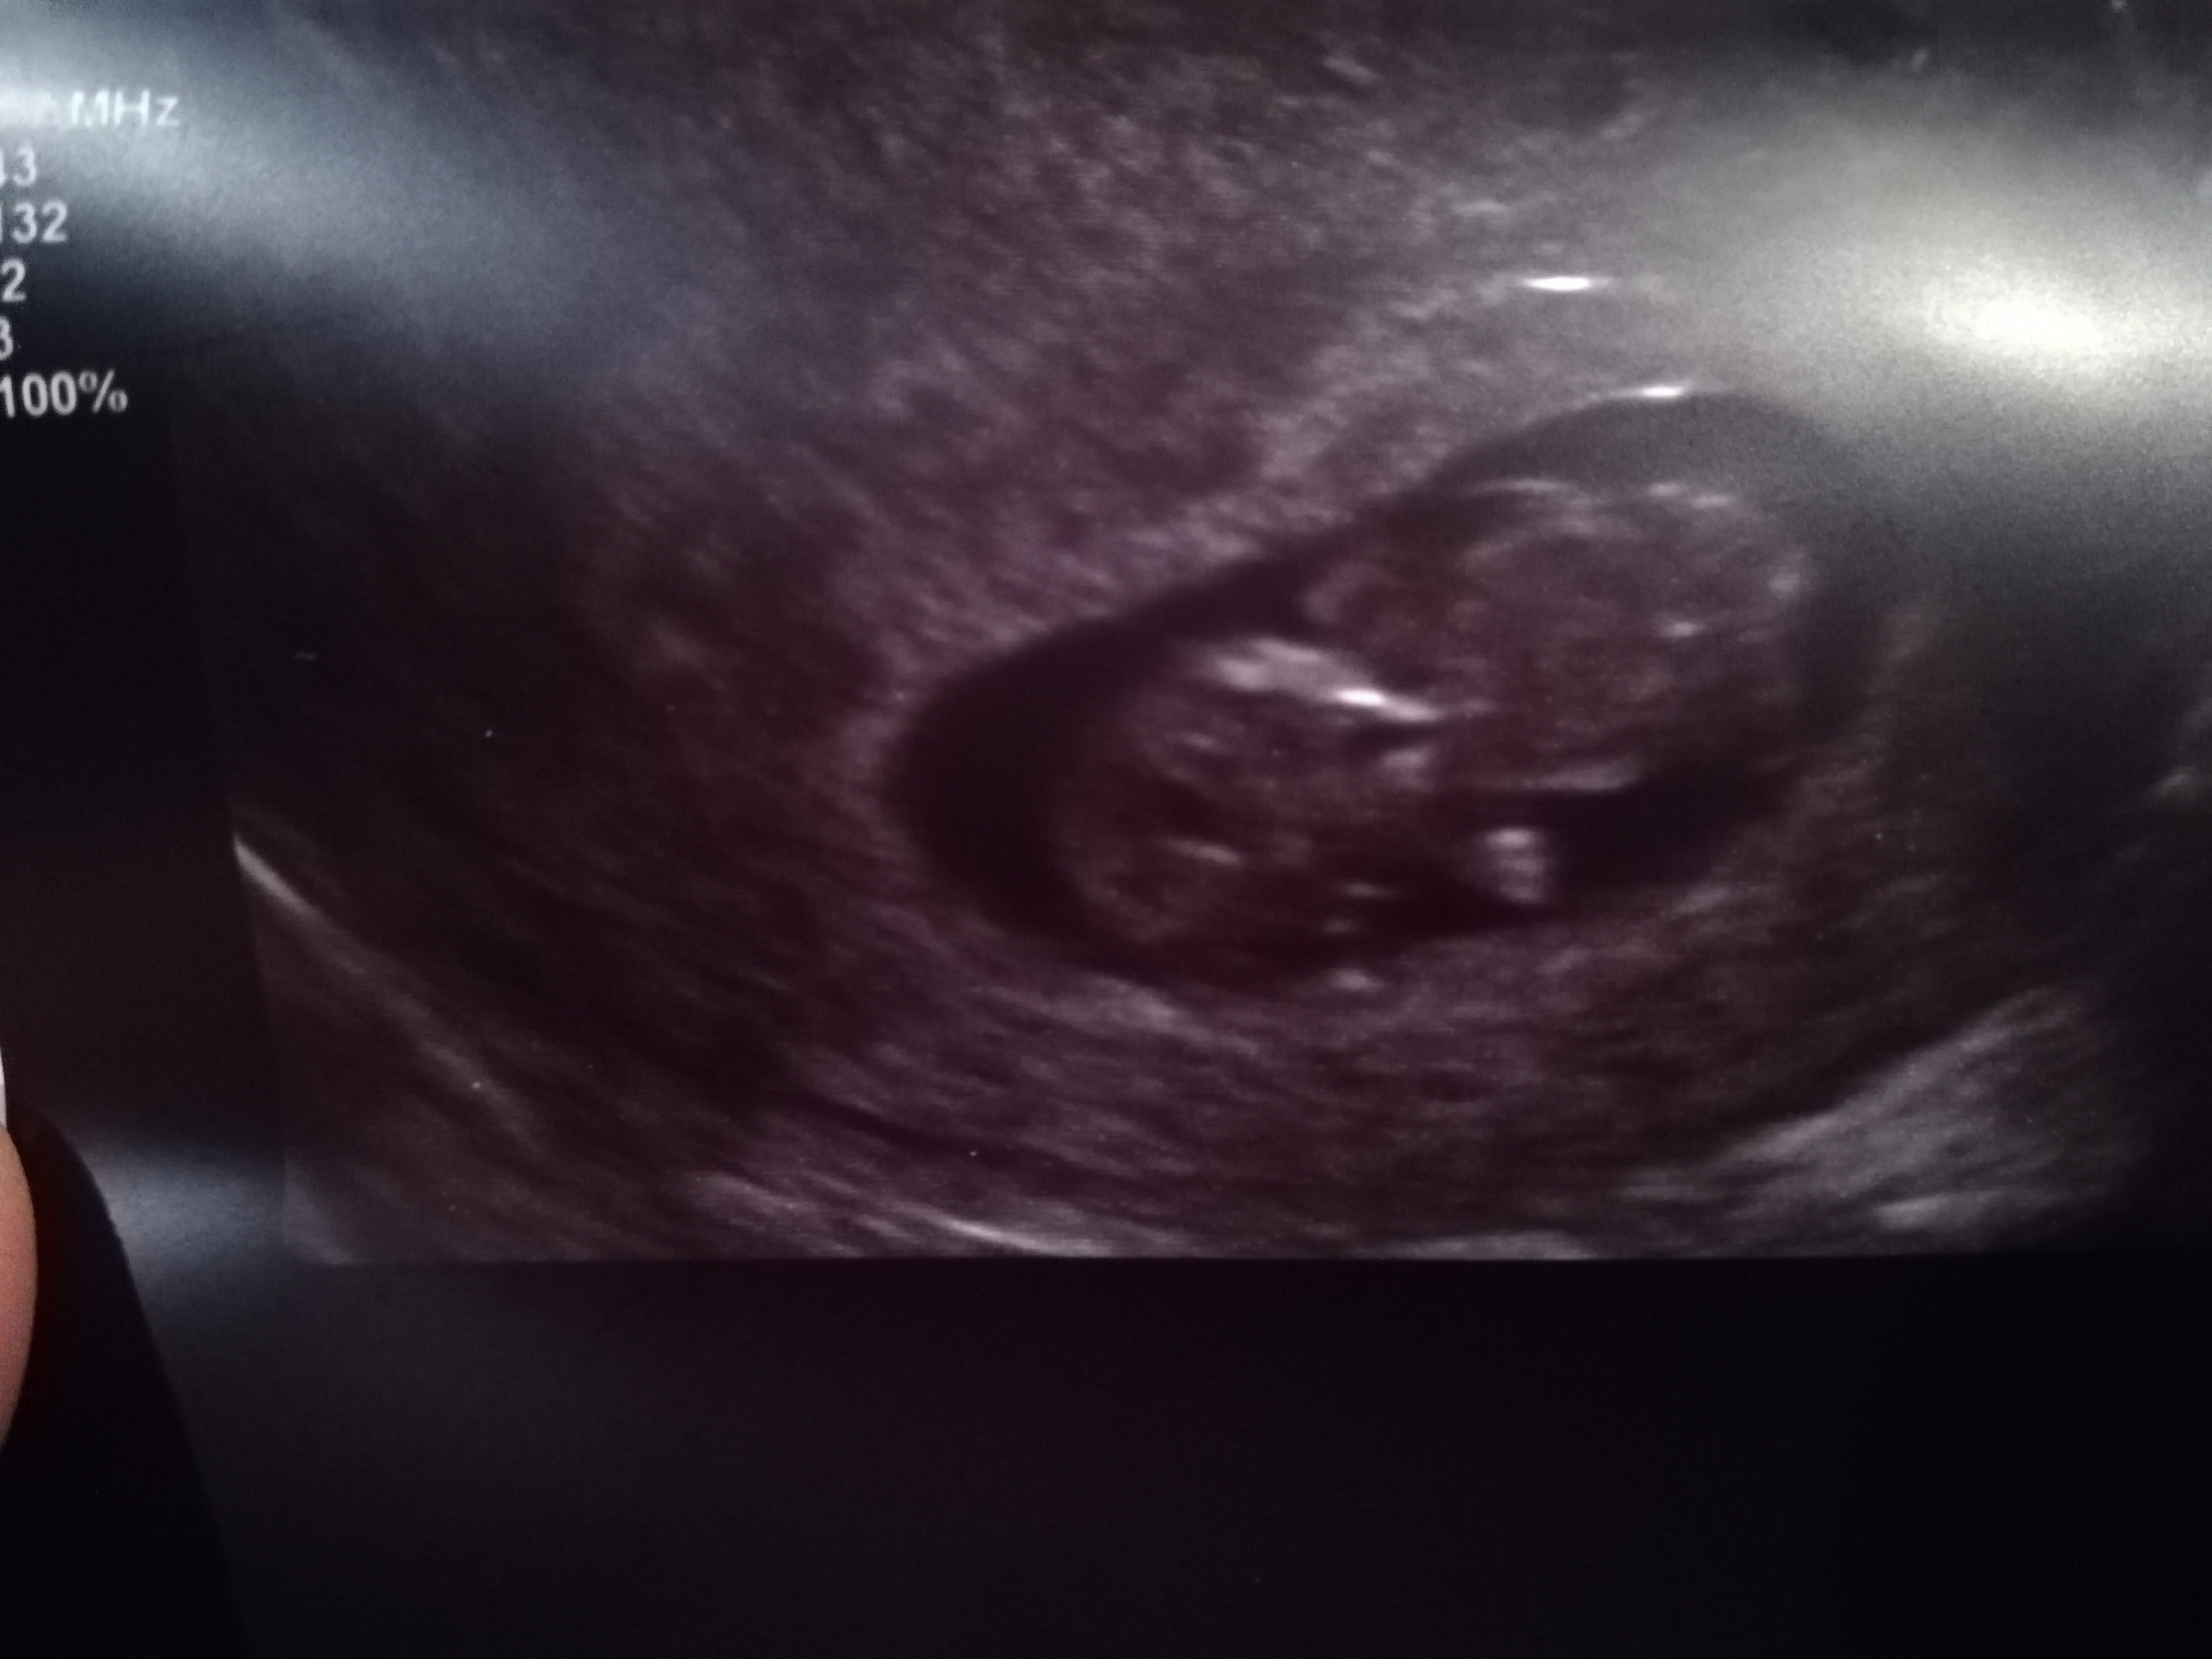

No kochane ja wczoraj miałam wizytę z dzidziusia wszystko ok. Moje mdłości i wymioty powoli ustępują mamy 10 tydzień. Niestety muszę iść do endokrynologa ponieważ nie wyszedł mi wynik w normie dla kobiet w ciąży. Dzidziuś ma 3 cm i ma się dobrze. A oto i on.. Współczuję tym które poronily Wiem co czujecie bo ja też to przeszłam w 2013 roku przed urodzeniem córki Lenki.

Załączniki

• IMG_20181029_182627.jpg

IMG_20181029_182627.jpg

953,3 KB · Wyświetleń: 169